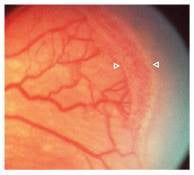

Página 323 - 9.3. Evolución de la ROP